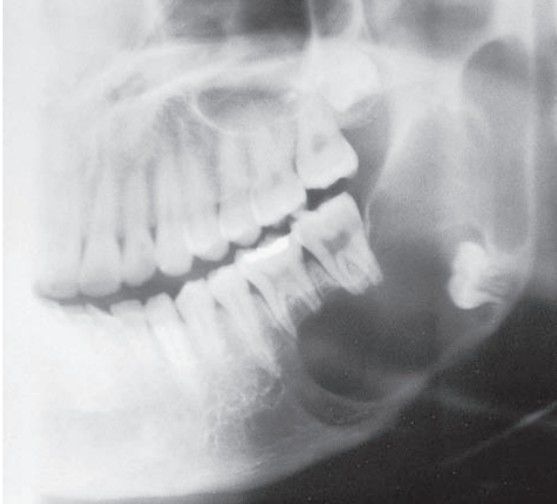

Ameloblastoma

Fourth and fifth decades; mandibular molar-ramus area most common site.